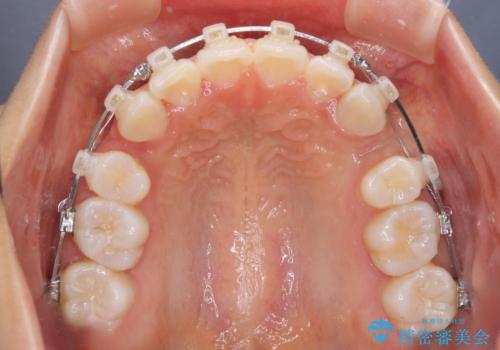

- クリアブラケット

- 出っ歯とデコボコを気にして来院された患者様です。

口元の突出感を改善するため、上下左右第一小臼歯4本の抜歯を行い、ワイヤー装置による矯正治療を行うこととしました。

治療前の上下正中はずれていましたが、骨格的な上下左右差はあまり認められなかったため、正中を揃えて治療を終えることができました。

1年半ほどで治療を終えることができるとは我々も想像しておらず、患者様には大変満足していただきました。